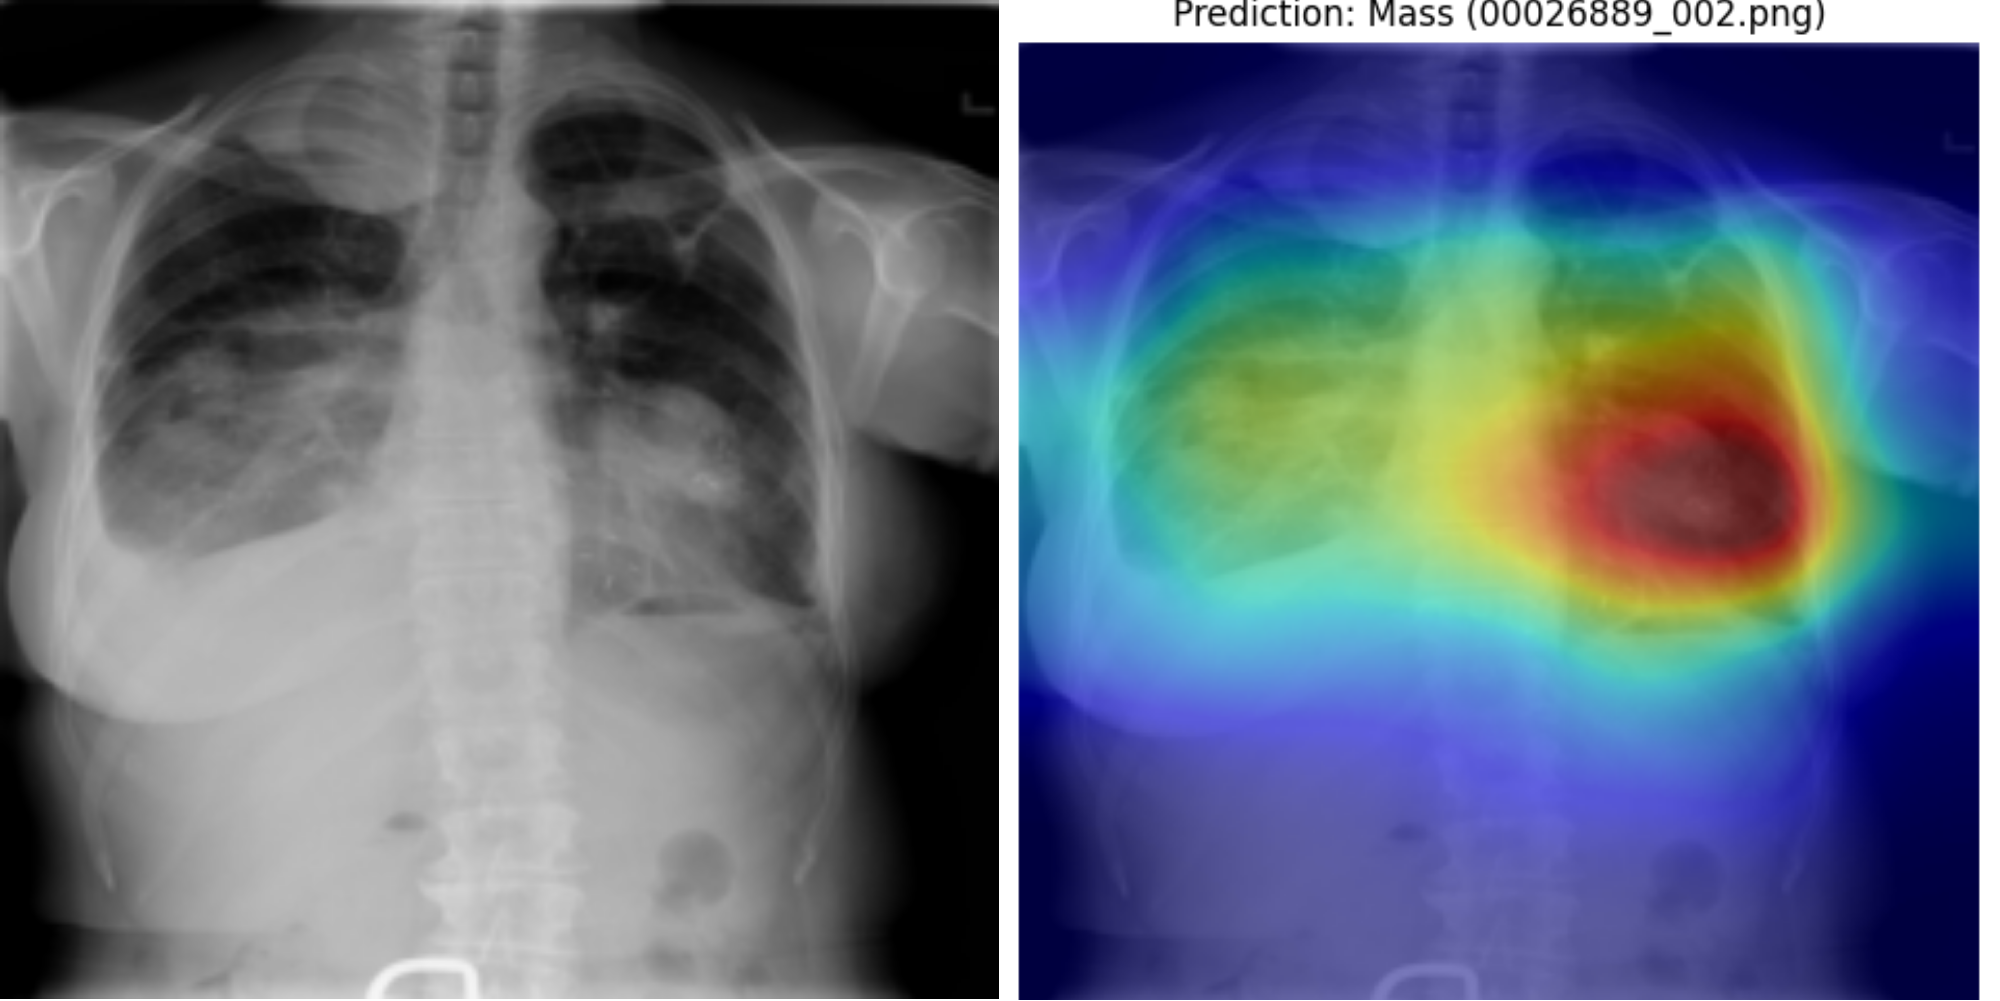

Achieved a mean ROC-AUC of 0.75 with a 27% reduction in false negatives across 112,120 chest X-rays, through class imbalance techniques, containerised pipeline deployment, and fully reproducible evaluation.